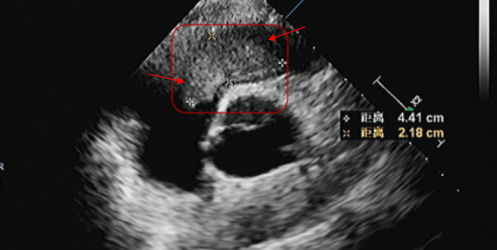

(术前影像显示,心腔内粘液瘤已明显增大)

去年8月,李先生又感到胸闷及活动后气短,检查发现在右心室流出道又有新发粘液瘤,随后去外院就诊,进行了基因检测,提示为卡尼综合征(Carney 综合征)。近期自觉症状加重,超声检查显示肿瘤明显增大,堵塞右心室流出道血流,还有明显的三尖瓣关闭不全。为寻求进一步治疗,李先生慕名来到西安高新医院心脏大血管外科。